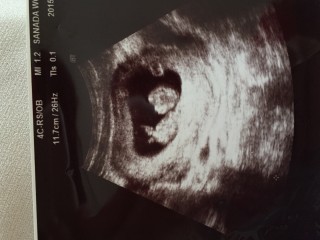

待望の2人目(^^) まだまだ性別が分かりませんが、 今から楽しみで仕方がありません(^^) 出血がありますが、順調なようで安心(^^)

14年振りの妊婦生活。円錐手術、ハードな仕事の為出血がある度に不安になりますが健診での赤ちゃんは元気ですよとの言葉にいつも安堵しています。この時は出血しない様にとお尻からのエコーでした!恥ずかしかったけど赤ちゃん元気で嬉しい♪人らしくなってきました。